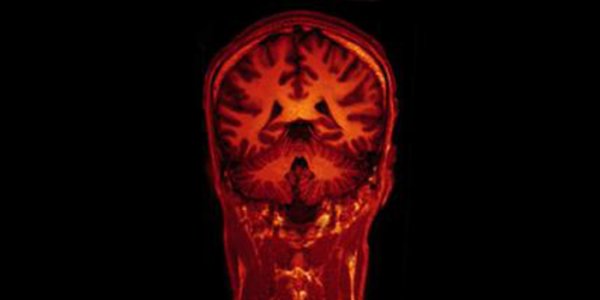

The size of the human brain expanded dramatically during the course of evolution, imparting us with unique capabilities to use abstract language and do complex math. But how did the human brain get…